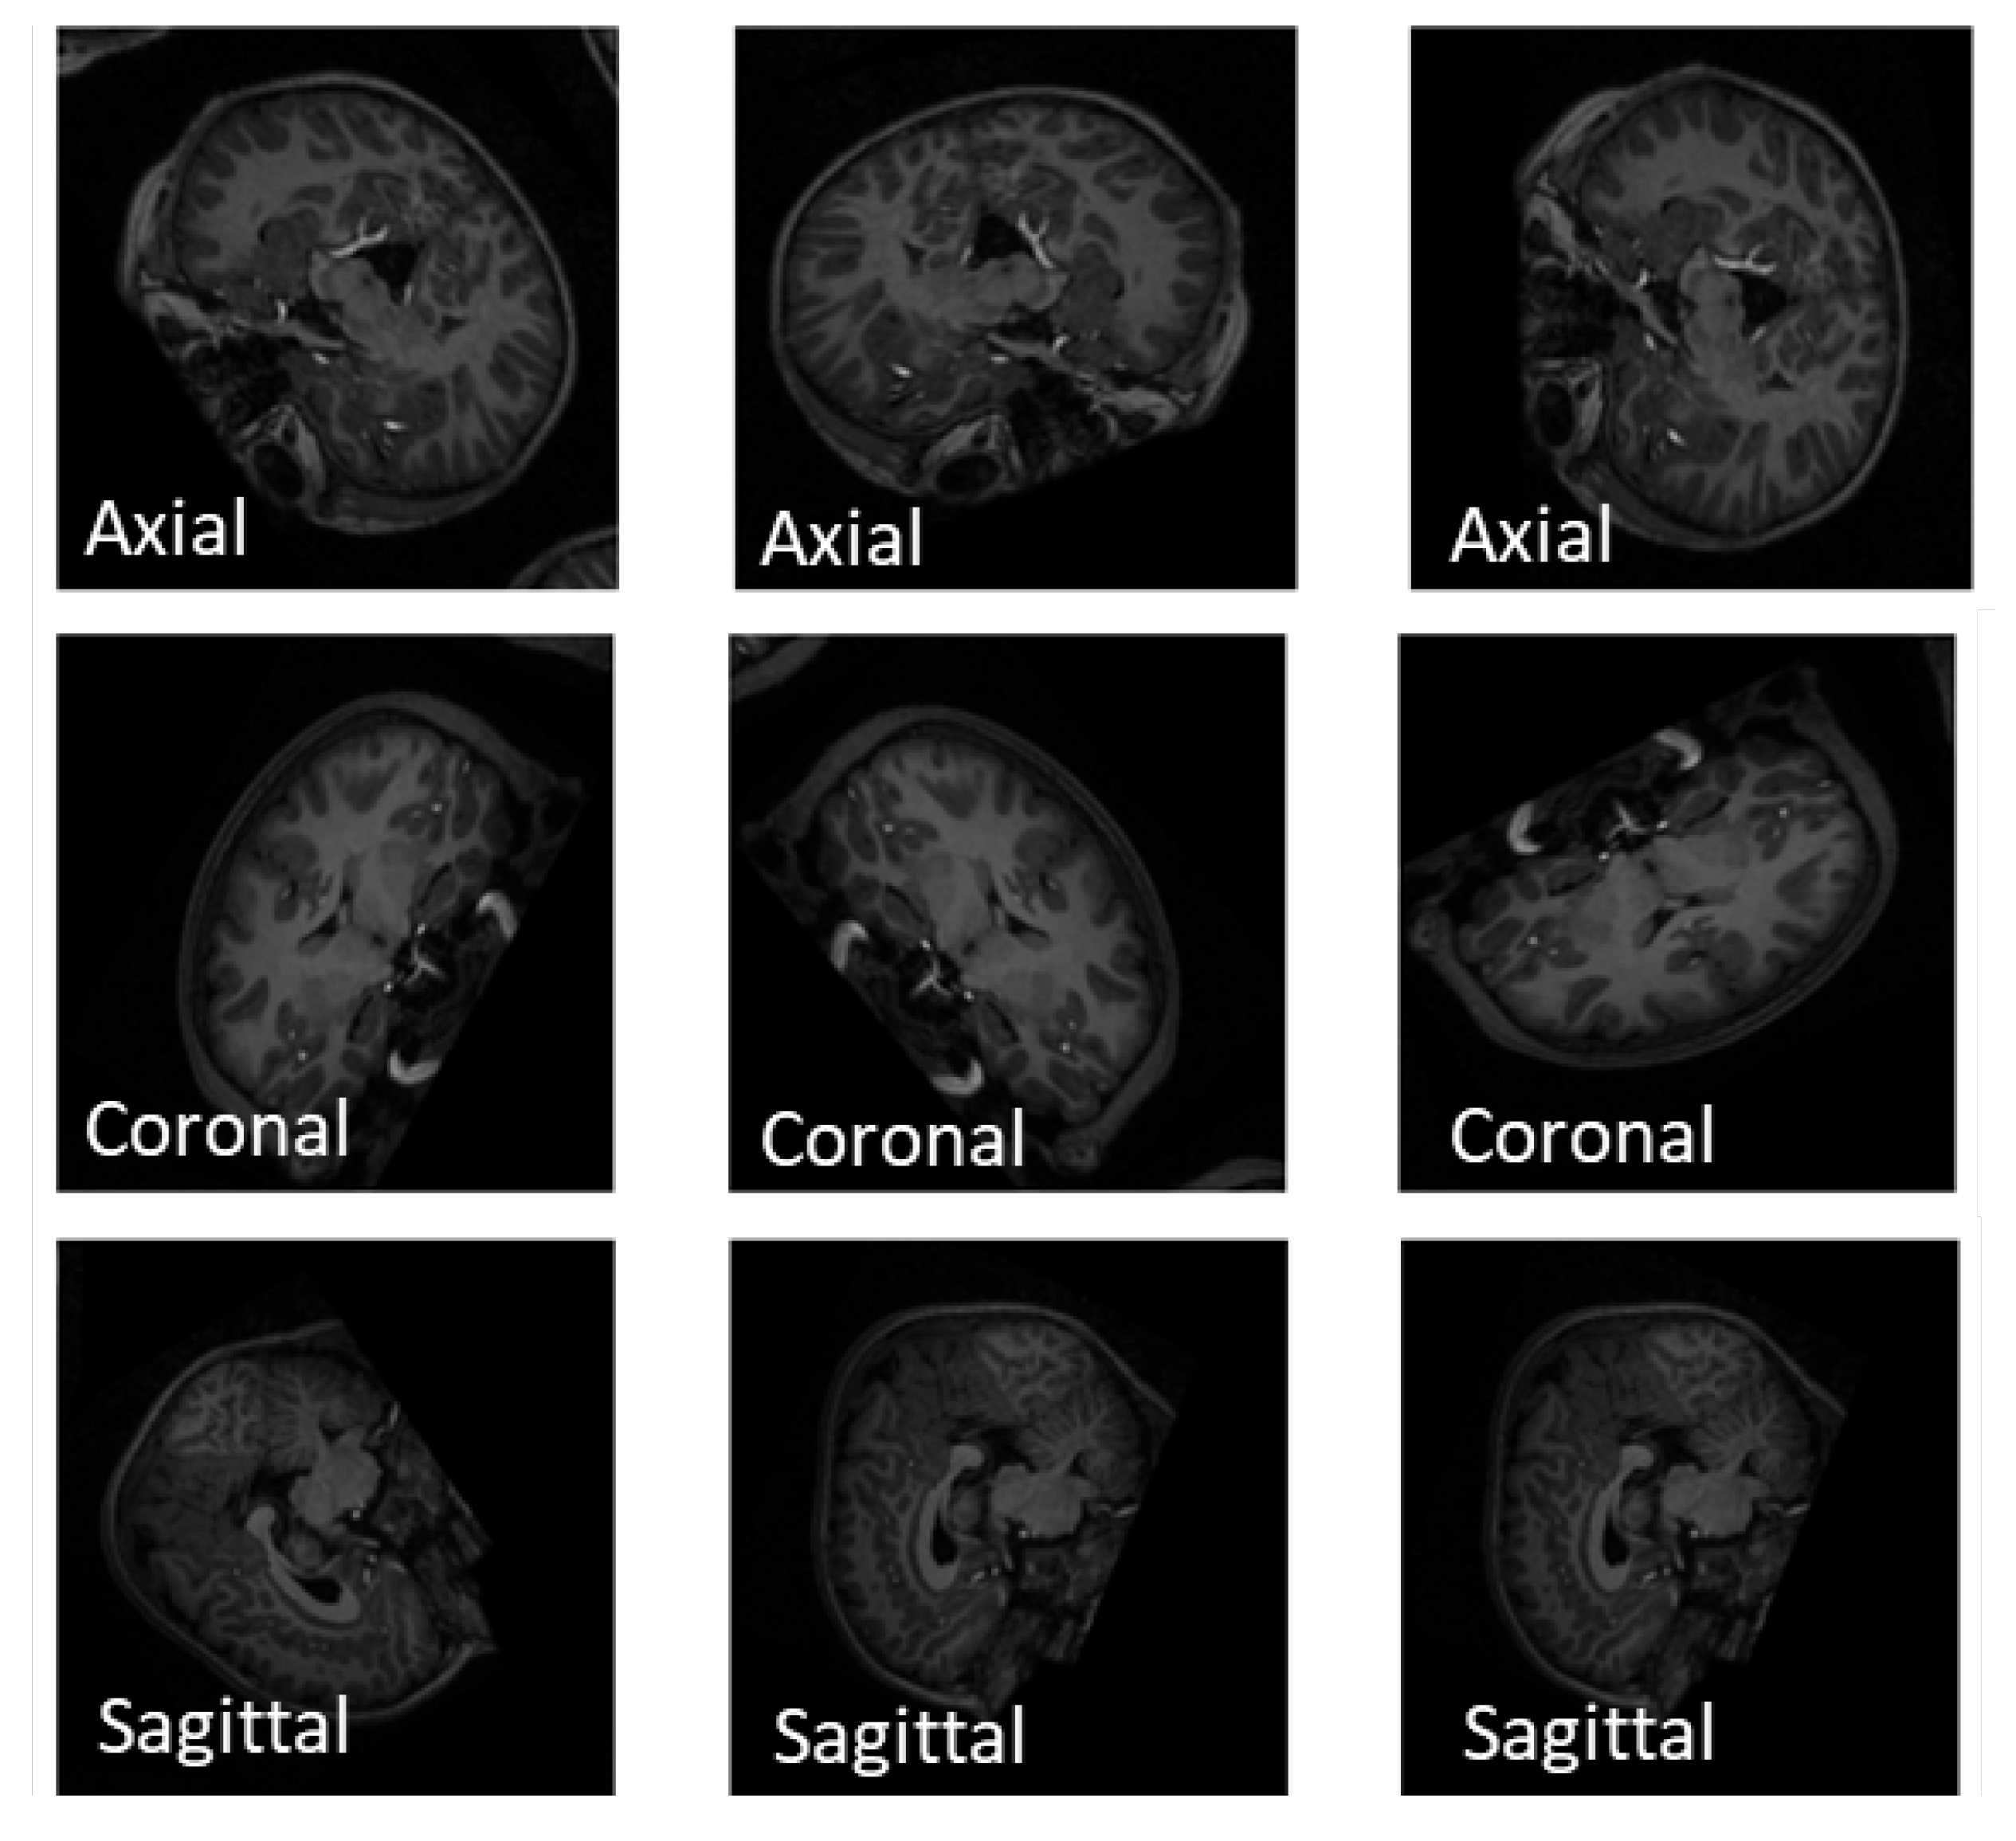

- Extracting 1, 10, and 50 slices along each brain plane (axial, sagittal, and coronal) to generate sequences of 2D images from raw 3D sMRI scans.

- Extracting 10, 30, and 50 slices along all brain planes (axial, sagittal, and coronal) to generate sequences of 3D images from raw 4D fMRI scans.

- Extracting all slices or giving some exceptions to the beginnings and the ends along all brain planes (axial, sagittal, and coronal) to generate sequences of 3D images from 3D sMRI and 4D fMRI scans.